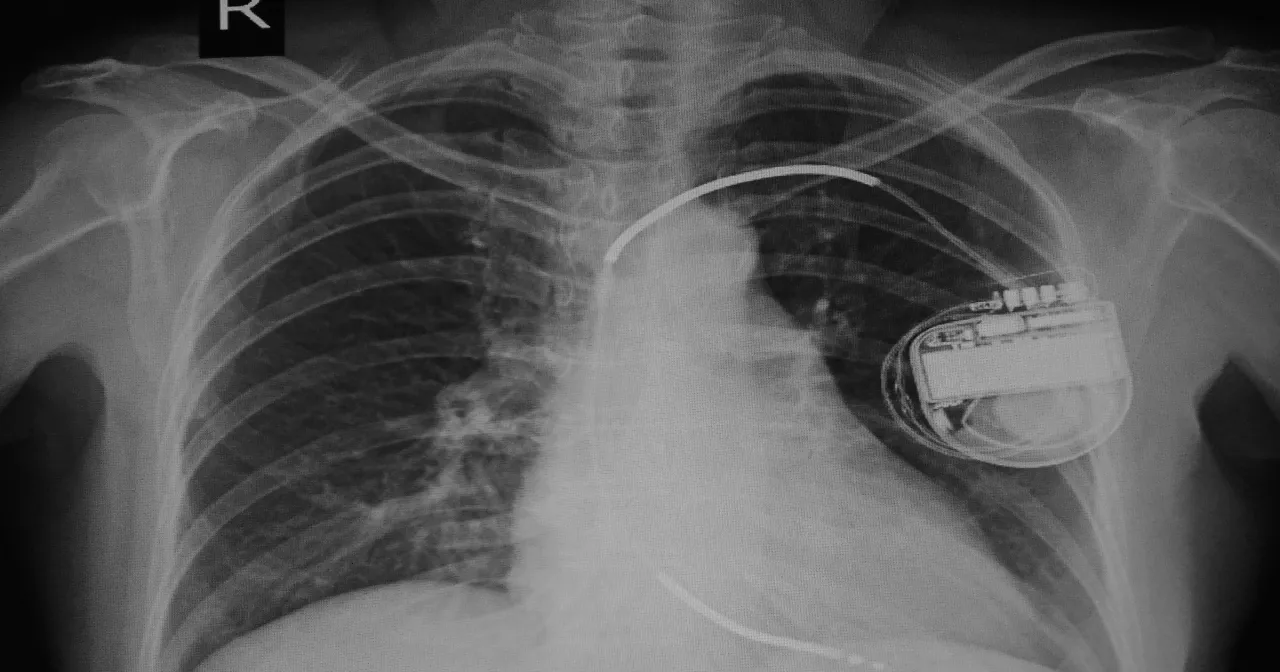

Wszczepialny kardiowerter-defibrylator, w skrócie ICD (z ang. Implantable Cardioverter-Defibrillator), to zaawansowane urządzenie medyczne, które pełni kluczową rolę w ratowaniu życia pacjentów zagrożonych nagłym zatrzymaniem krążenia. Jego podstawową funkcją jest ciągłe monitorowanie rytmu serca. Jeśli ICD wykryje niebezpieczne arytmie, takie jak migotanie komór czy szybki częstoskurcz komorowy, automatycznie dostarcza impulsy elektryczne od stymulacji antyarytmicznej po defibrylację aby przywrócić prawidłowy rytm serca. To właśnie ta zdolność do szybkiej interwencji sprawia, że kardiowerter-defibrylator jest niezastąpiony w prewencji nagłej śmierci sercowej u wielu pacjentów. Z mojego doświadczenia wiem, że dla wielu osób jest to dosłownie druga szansa na życie.Kto jest kandydatem do zabiegu? Główne wskazania medyczne, o których musisz wiedzieć

Klasyczny kardiowerter-defibrylator przezżylny to obecnie najczęściej stosowany typ urządzenia. Charakteryzuje się tym, że elektrody, które monitorują rytm serca i dostarczają impulsy, są wprowadzane do serca przez naczynia żylne. Są one umieszczane w odpowiednich jamach serca przedsionku i/lub komorze. To rozwiązanie jest bardzo skuteczne i od lat stanowi złoty standard w leczeniu pacjentów zagrożonych nagłym zatrzymaniem krążenia. Jego cena jest zazwyczaj niższa niż bardziej zaawansowanych technologicznie alternatyw.

Podskórny defibrylator S-ICD (z ang. Subcutaneous Implantable Cardioverter-Defibrillator) to nowocześniejsza alternatywa dla klasycznego ICD. Kluczową różnicą jest to, że elektroda jest umieszczana podskórnie wzdłuż mostka, a nie wewnątrz serca. Eliminuje to ryzyko powikłań związanych z elektrodami wewnątrzsercowymi, takich jak infekcje czy uszkodzenia naczyń. Chociaż technologia S-ICD jest droższa niż klasyczny ICD, to w Polsce od 2019 roku jej implantacja jest świadczeniem gwarantowanym. Co więcej, w ramach Krajowej Sieci Kardiologicznej jest ona w pełni refundowana i nielimitowana, co stanowi bardzo ważną informację dla pacjentów, którzy kwalifikują się do tego typu urządzenia.

Kardiowerter-defibrylator z funkcją terapii resynchronizującej (CRT-D, z ang. Cardiac Resynchronization Therapy Defibrillator) to najbardziej zaawansowane i jednocześnie najdroższe urządzenie. Jest ono przeznaczone dla pacjentów z zaawansowaną niewydolnością serca, u których występuje dyssynchronia skurczu komór. Oprócz standardowej funkcji defibrylacji, CRT-D posiada dodatkowe elektrody, które stymulują obie komory serca jednocześnie, poprawiając ich synchronię. Dzięki temu serce pracuje efektywniej, co przekłada się na lepszą wydolność serca, zmniejszenie objawów niewydolności i znaczną poprawę jakości życia pacjenta. Ze względu na swoją złożoność i dodatkowe funkcje, jest to najdroższa opcja na rynku.